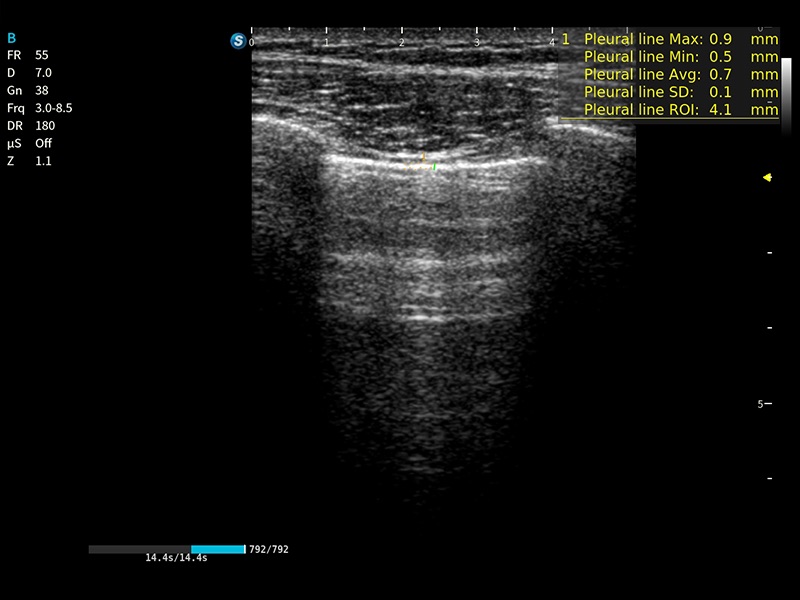

作为开立医疗全新打造的高端床旁笔记本超声,E11不仅具备卓越的图像质量,同时搭载全面高效的自动测量工具,助力医生实现更快速、更精准的床旁诊断。

E11搭载了丰富的自动化测量工具,以及专为POC科室定制的高级功能;同时配备了为急诊医师量身打造的 SonoFast急重症超声流程,以帮助临床医生最大限度的提升工作效率